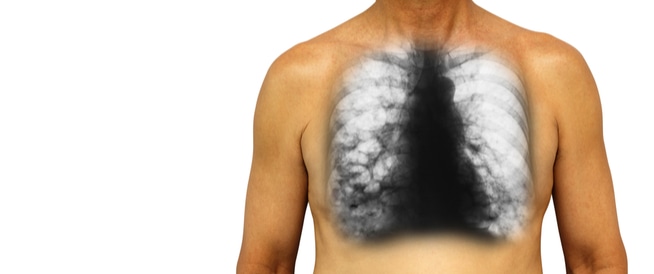

يتم التشخيص بالتصوير الإشعاعي المقطعي المحوسب (CT) للصدر، ومرة بواسطة تصوير القصبات الظليل (bronchography) (تسريب ماده تبايُن للقصبات).

يمكن أن يتم تفسير الصورة الاعتيادية للصدر على أنه طبيعي، أو يمكن رصد علامات شاذة فيه. بالإضافة إلى التصوير، يجب إجراء زرع لفحص خزعة من البلغم ولأداء الجهاز الرئوي.